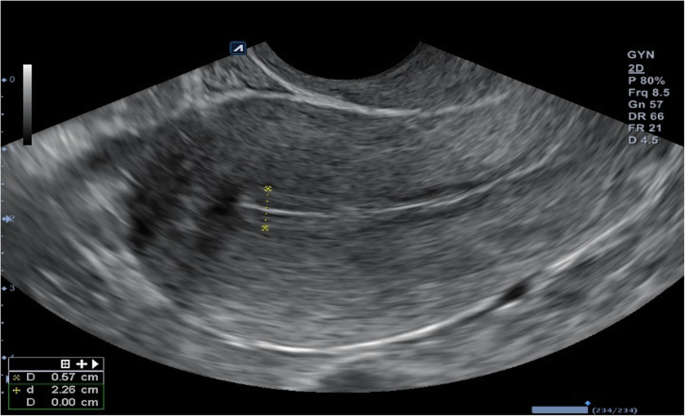

On the day of hysteroscopy, the patient began to take estradiol valerate 2.0 mg, at two tablets daily by mouth. After 3 days, a gel of estradiol hemihydrate 1.0 mg was added, one sachet daily transdermally. Thirteen days after hysteroscopy, ultrasound monitoring of the endometrium was performed, and progesterone 200 mg was prescribed, one tablet three times daily by mouth. On the sixth day of the progesterone application, the thickness of the patient’s endometrium was 0.63 cm after ultrasound monitoring (Figs. 4 and 5). At the patient’s insistence, two embryos were transferred that day.